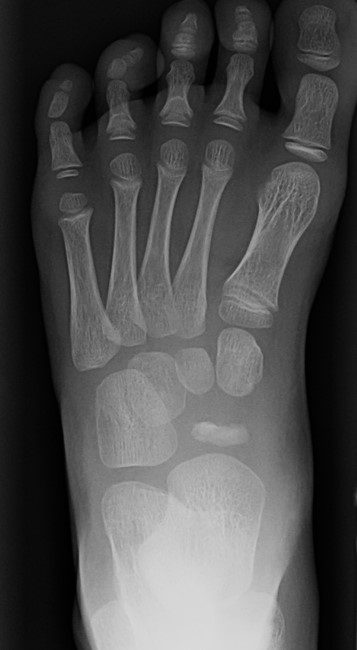

X-ray

Flattening / sclerosis / fragmentation of navicular